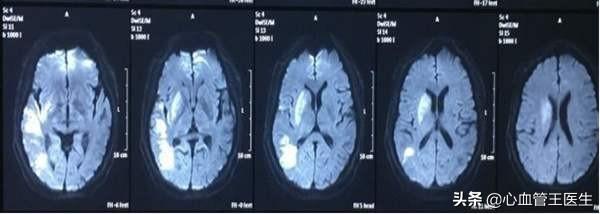

海綿体梗塞と呼ばれるもう一つのタイプの脳梗塞は、脳梗塞の特殊な形態に属する最も一般的なもので、すなわち、脳動脈の末端が閉塞し、わずか3〜15mmの範囲の脳組織が壊死するものである。海綿状梗塞は機能的な部位に起こり、めまい、唾液分泌、ろれつが回らない、軽度の顔面神経麻痺、不安定な歩行などの軽い一過性の症状を示すことがある。多くは非機能部位に発生し、発生しても患者は感覚も症状も全くなく、頭蓋CTやMRIによる身体検査後に初めて発見される。主に加齢と高血圧が関係している。発症の原因には諸説あるが、主に末梢動脈の老化が関係している。